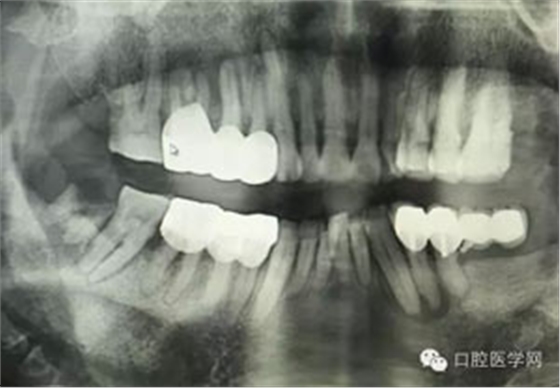

病例1:患者迫切希望保留自己的這一顆牙齒,根尖周陰影比較大,二度松動(dòng).而且旁邊有種植修復(fù)體,和患者溝通好后,治療好后觀察一個(gè)月后冠修復(fù),因?yàn)橛蟹N植的后期修復(fù),所以有了機(jī)會(huì)觀察,術(shù)后三個(gè)月和術(shù)后四個(gè)月,根尖恢復(fù)的還算不錯(cuò),希望能夠繼續(xù)觀察下去.這樣子的病例,做的時(shí)候我們一定要非常的小心,和患者要有充分的溝通以及不同科室的溝通然后決定怎么樣做比較好,假如就是出現(xiàn)了問(wèn)題,到時(shí)候我們也比較好處理些,免得我們自己到時(shí)候不好收?qǐng)觥?/span> 病例2:364647中齲的樹(shù)脂充填,現(xiàn)在樹(shù)脂的充填材料非常之多,有些時(shí)候,我們感覺(jué)有了好的材料我們就可以做出好的修復(fù),可是這是在我們有扎實(shí)的基本功的基礎(chǔ)上的,我們可以沒(méi)有那么好的樹(shù)脂,那么多的顏色選擇,修復(fù)的那么的逼真,但是我們至少要恢復(fù)患者牙齒的功能,將腐質(zhì)去除干凈,薄壁弱尖消除掉,選擇好適應(yīng)癥,給患者以盡可能好的修復(fù)。 來(lái)源于KQ88